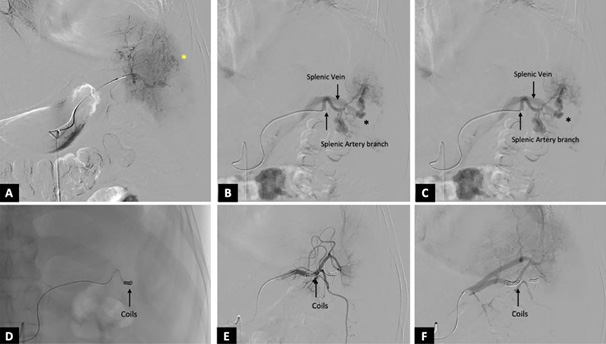

CT angiography (CTA) of the abdomen revealed multiple splenic contusions with over 30% non-enhancing parenchyma in the mid and lower poles, indicating devascularization. Several pseudoaneurysms were identified, along with early opacification of the splenic vein in the arterial phase – s/o splenic AVF (Figure 1, A–F).

Under aseptic conditions, proper transfemoral arterial access was achieved by using a 6F vascular sheath. The celiac trunk and selective splenic artery angiogram revealed an abnormal intrasplenic contrast blush with multiple pseudoaneurysms from the lower pole branches of the splenic artery, demonstrating early opacification of the splenic vein. Super-selective catheterisation of the affected lower pole branch was performed by using a microcatheter. A frame coil (8 mm) was initially deployed to reduce the arterial flow, followed by several smaller coils measuring 2 mm and 3 mm in diameter to attain complete occlusion. Post-embolisation angiography showed no opacification of the lower pole branches, AVF, and pseudoaneurysms, while preserving the perfusion of the unaffected upper splenic pole.